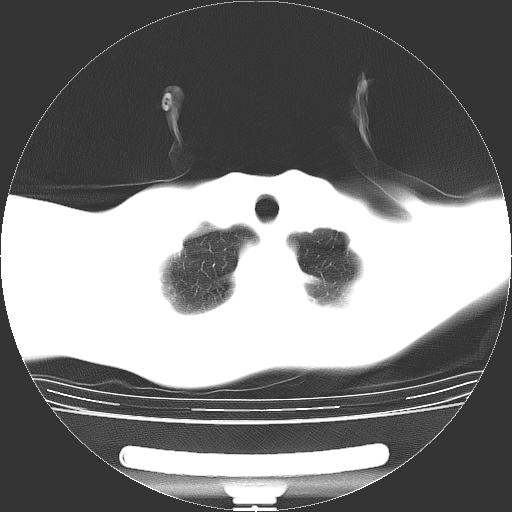

标题: CT19767:男,20岁,右侧气胸行闭式引流术后五天CT检查。 [打印本页]

标题: CT19767:男,20岁,右侧气胸行闭式引流术后五天CT检查。

男,20岁,右侧气胸行闭式引流术后五天ct检查看肺内是否有肺大泡,纵隔窗未见异常,未上传。